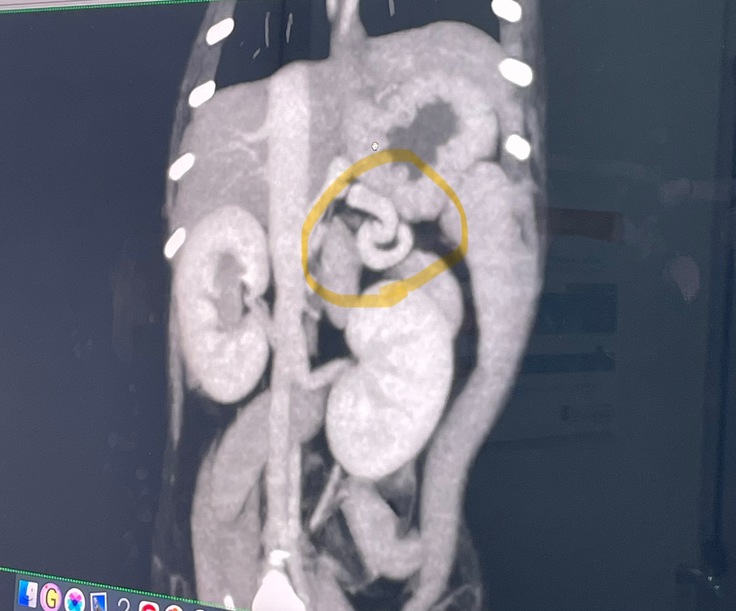

1回目の手術の写真です。

※2枚目に【手術中の写真】があります。

苦手な方はご注意ください

想像を超える大手術。生後6ヶ月の小さな体でこの手術を2回も行わなければ、ぱんちゃんは助かりません涙